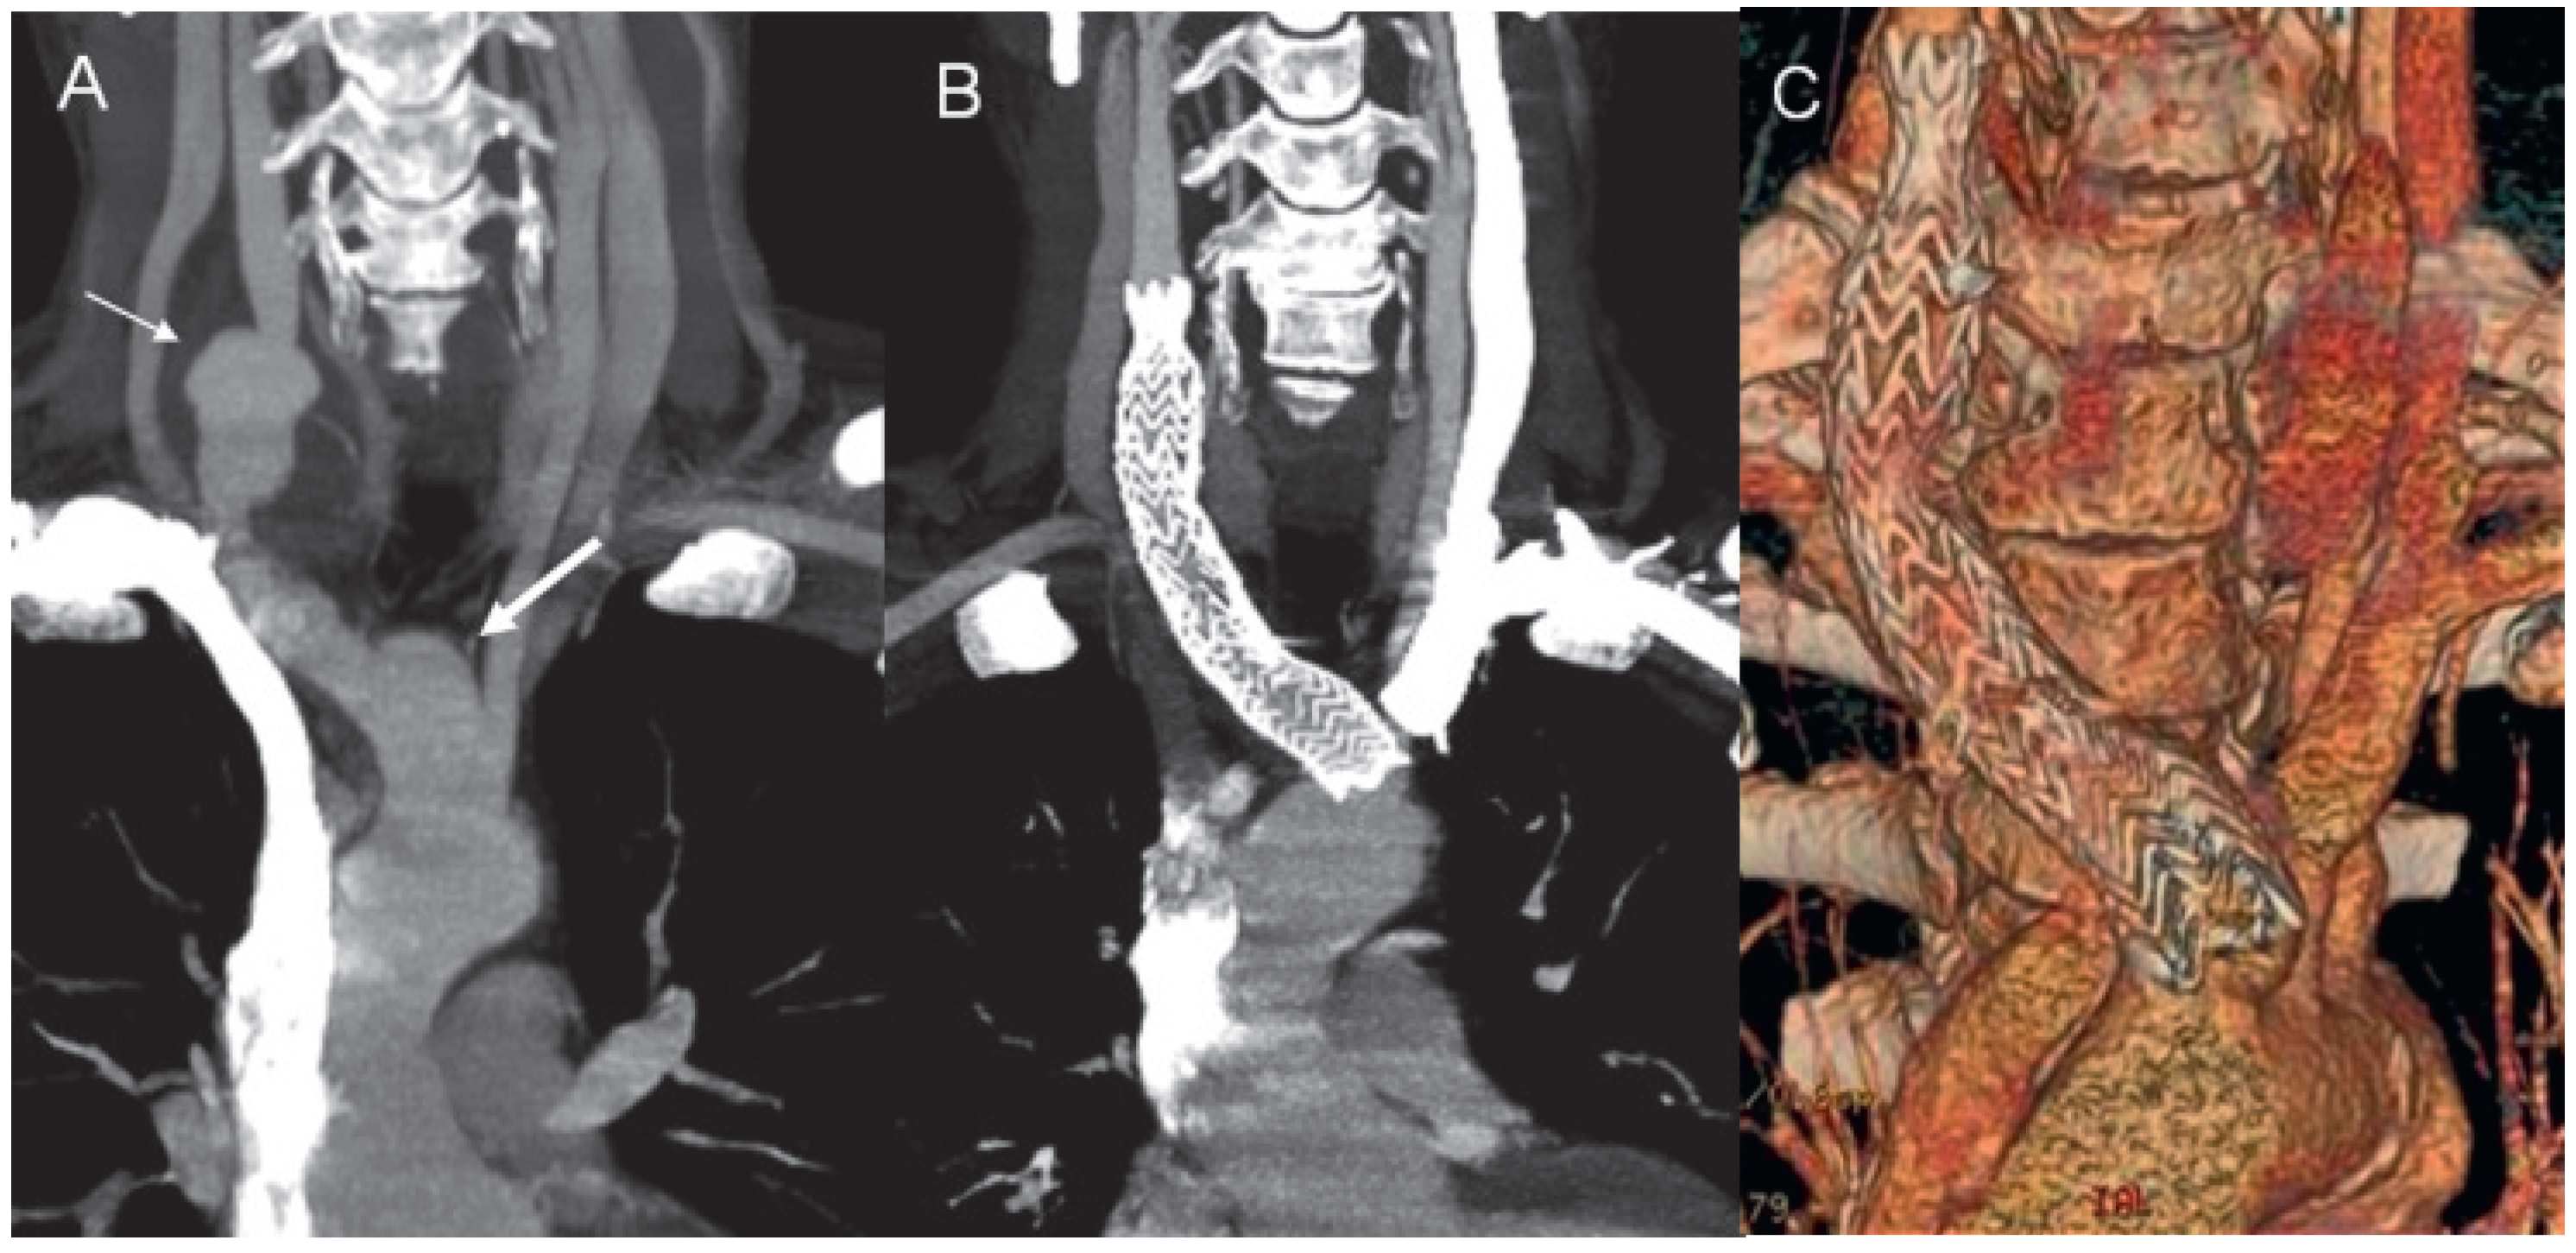

Figure 3.

A) CT angiography in a minimal intensity projection modality showing the aneurysm of the innominate artery (thick arrow) and the right commune carotid artery (thin arrow). CT angiography in a minimal intensity projection modality (B) and a 3D volume rendering reconstruction (C) demonstrate the correct positioning of the stent.

Therapy with steroids, mycophenolate and cyclosporin did not result in a desirable improvement. On the basis of the fact that PG was responsive to local tacrolimus, the probative treatment with oral tacrolimus at a dosage of 3 mg/b.i.d., on top of steroids and mycophenolate, was attempted. It resulted in a rapid clinical improvement and regression of inflammation documented with 18FDG PET after four months. Six months later, the patient presented with pain in the right supraclavicular region and presence of a pulsating tumour. CT angiography revealed an aneurysm of the innominate artery (maximal diameter of 24 mm) expanding to the right carotid commune artery (maximal dimensions of 24 × 33 mm) with wall thickening and suspected thrombus adherent to the wall of the aneurysm (Figure 2, panel D). Mild dilatation of the ascending aorta (44 mm), not observed on the previous CT scan, was also documented. The patient continued immunosuppressive treatment and clopidogrel was introduced. The possibility of endovascular retrograde covered stenting was discussed with the patient. Due to further expansion of the right carotid commune artery aneurysm (increased to maximal dimensions of 35 x 46 mm), the intervention was successfully performed two months later (January 2007) with good positioning of the stent and without signs of leaking (Figure 3). The patient continued immunosuppressive therapy with subsequent periodical radiological and duplex controls. He had two relapses of PG, which required hospitalisation, in the next two years. In 2009, routine echocardiography revealed expansion of the ascending aorta from 44 to 50 mm leading to severe aortic regurgitation, and dilatation of the left ventricle. Coronary angiography was performed and showed a co-lateralised occlusion of the right coronary artery and non-significant plaque in the left anterior descending artery. In November 2009, aortic valve and ascending aorta replacement as well as single aorto-coronary by-pass graft surgery was performed. Histological analysis of an aortic specimen showed degeneration of media, adventitial fibrosis with lymphocyte infiltration. Although these findings were not specific for TA and could be found in other forms of vasculitis, it is known that a negative biopsy does not definitely rule out the diagnosis of TA.